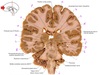

9

Q

a

Body of corpus callosum

10

b

septum pellucidum

11

c

Corona radiata

12

d

Anterior horn of lateral ventricle

13

e

Globus pallidus

14

f

Anterior commissure

15

g

Optic chiasm

16

h

Optic tract

17

i

Uncus

18

j

19

k

20

L

Putamen

21

m

Anterior limb of internal capsule

22

n

Head of caudate nucleus